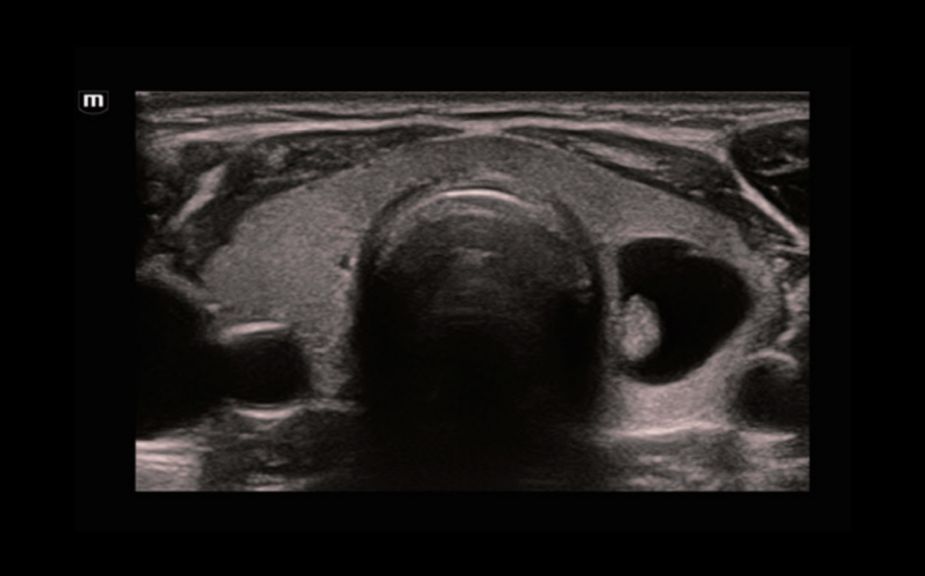

Диагностика очаговых поражений с помощью контрастов: контраст-усиленная визуализация UWN+

Использование как второй гармоники, так и нелинейных фундаментальных сигналов

Высокая чувствительность к низкоамплитудным сигналам и большее время персистенции контрастного вещества

КУУЗИ: метастатический рак печени

КУУЗИ: перфузия аденомы щитовидной железы